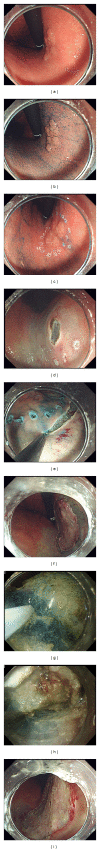

The prognosis for gastric cancer depends on its stage; so, detection in the early stage of disease is important, when complete and curative removal is possible. Accurate diagnosis can be facilitated by a sound understanding of the basic findings of white light endoscopy of early gastric cancer, and diagnosis can be refined further by the combined use of other imaging modalities such as image-enhanced endoscopy including chromoendoscopy and endoscopic ultrasonography. Minimally invasive endoscopic treatment has come to be the preferred therapeutic approach for early gastric cancer. In addition to conventional endoscopic mucosal resection, a new technique known as endoscopic submucosal dissection (ESD) has spread rapidly worldwide. Indeed, strategies for ESD have been established, devices developed, its indications expanded, and its safety and long-term results extensively reported. Some unique combination therapies involving endoscopy and surgical treatment have also been reported. It is anticipated that the number of patients undergoing endoscopic therapy will continue to increase, and the ongoing developments in endoscopic treatment are expected not only to improve gastric cancer prognosis but also to maintain good quality of life after treatment.